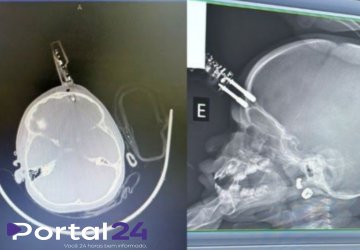

O acidente aconteceu na última terça-feira, dia 13, quando a mãe se ausentou por poucos instantes. Ao retornar, encontrou a filha ferida, com sangramento intenso na região da cabeça. A criança foi levada imediatamente ao hospital, onde exames de imagem apontaram perfuração craniana e indicaram a necessidade de cirurgia de emergência.

O procedimento foi realizado pelo neurocirurgião Bruno Castro, que efetuou a retirada cuidadosa do objeto, limpeza da área atingida, fechamento da lesão e reconstrução do local afetado. A rápida intervenção médica foi decisiva para evitar complicações mais graves.